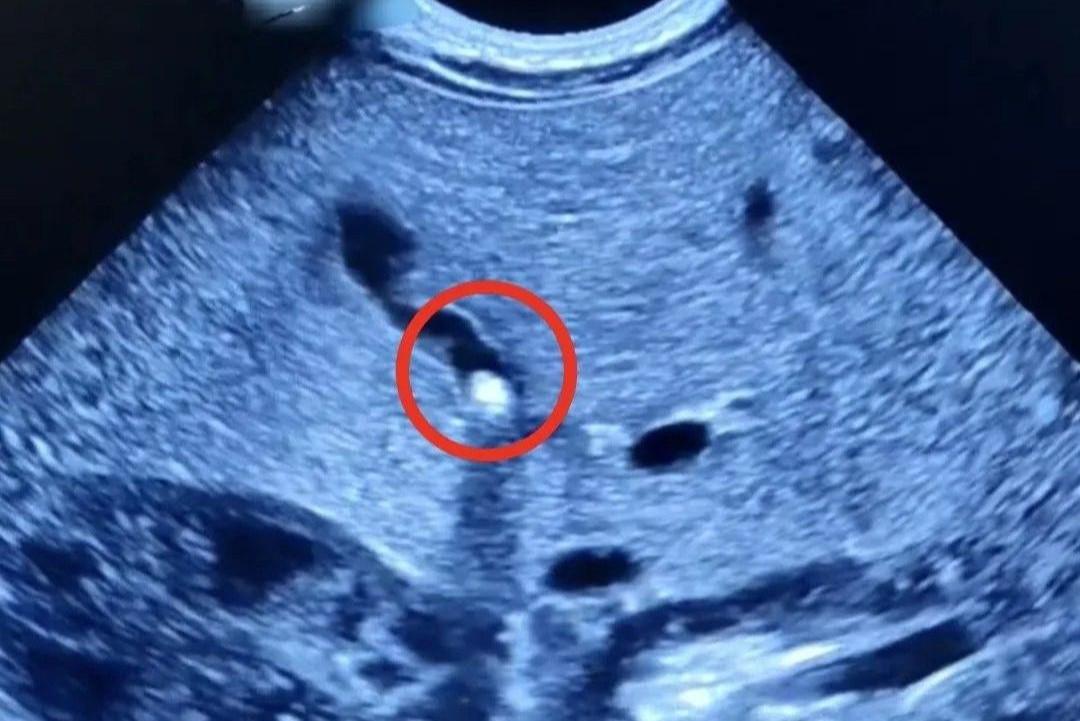

СаратовВсе новостиЖелчнокаменная болезнь

Новости по тегу: Желчнокаменная болезнь